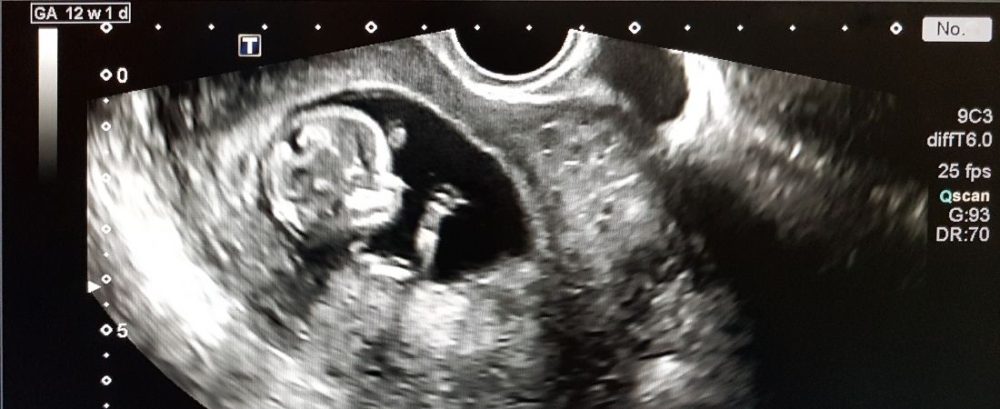

The unborn should be protected.

The unborn should be protected. Birth to a married man and woman provides children the best chance for success in life.